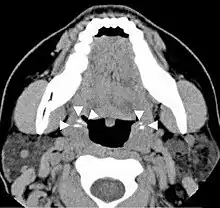

| A tonsillolith lodged in the tonsillar crypt | |

Imaging diagnostic techniques can identify a radiopaque mass that may be mistaken for foreign bodies, displaced teeth or calcified blood vessels. CT scan may reveal nonspecific calcified images in the tonsillar zone. The differential diagnosis must be established with acute and chronic tonsillitis, tonsillar hypertrophy, peritonsillar abscesses, foreign bodies, phlebolites, ectopic bone or cartilage, lymph nodes, granulomatous lesions or calcification of the stylohyoid ligament in the context of Eagle syndrome (elongated styloid process).[18]